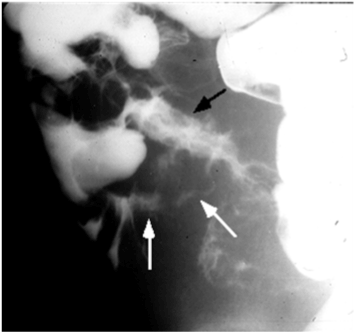

6. In your opinion, how can imaging studies (e.g.: x-ray, CT, MR enterography, and barium studies) help in identifying pathological findings from an anatomical view? Describe at least 3 radiologic findings that are characteristic of this disease (use radiographic images to demonstrate the findings). (Figure 3a-3c).

Figure 3a. White arrow showing string sign of the terminal ileum due to narrowing

Figure 3b. Black arrow showing terminal ileum. White arrows showing ileocecal fistula.